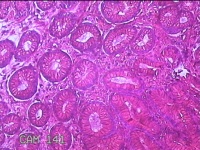

胃窦粘膜

性别

女

年龄

52岁

临床诊断

胃食管反流?;慢性胃炎

一般病史

吞咽困难2年余。

标本名称

大体所见

灰白粉红色组织小米大一团。

图1

有可能是慢性炎,片子这个效果,猜起来比较困难,